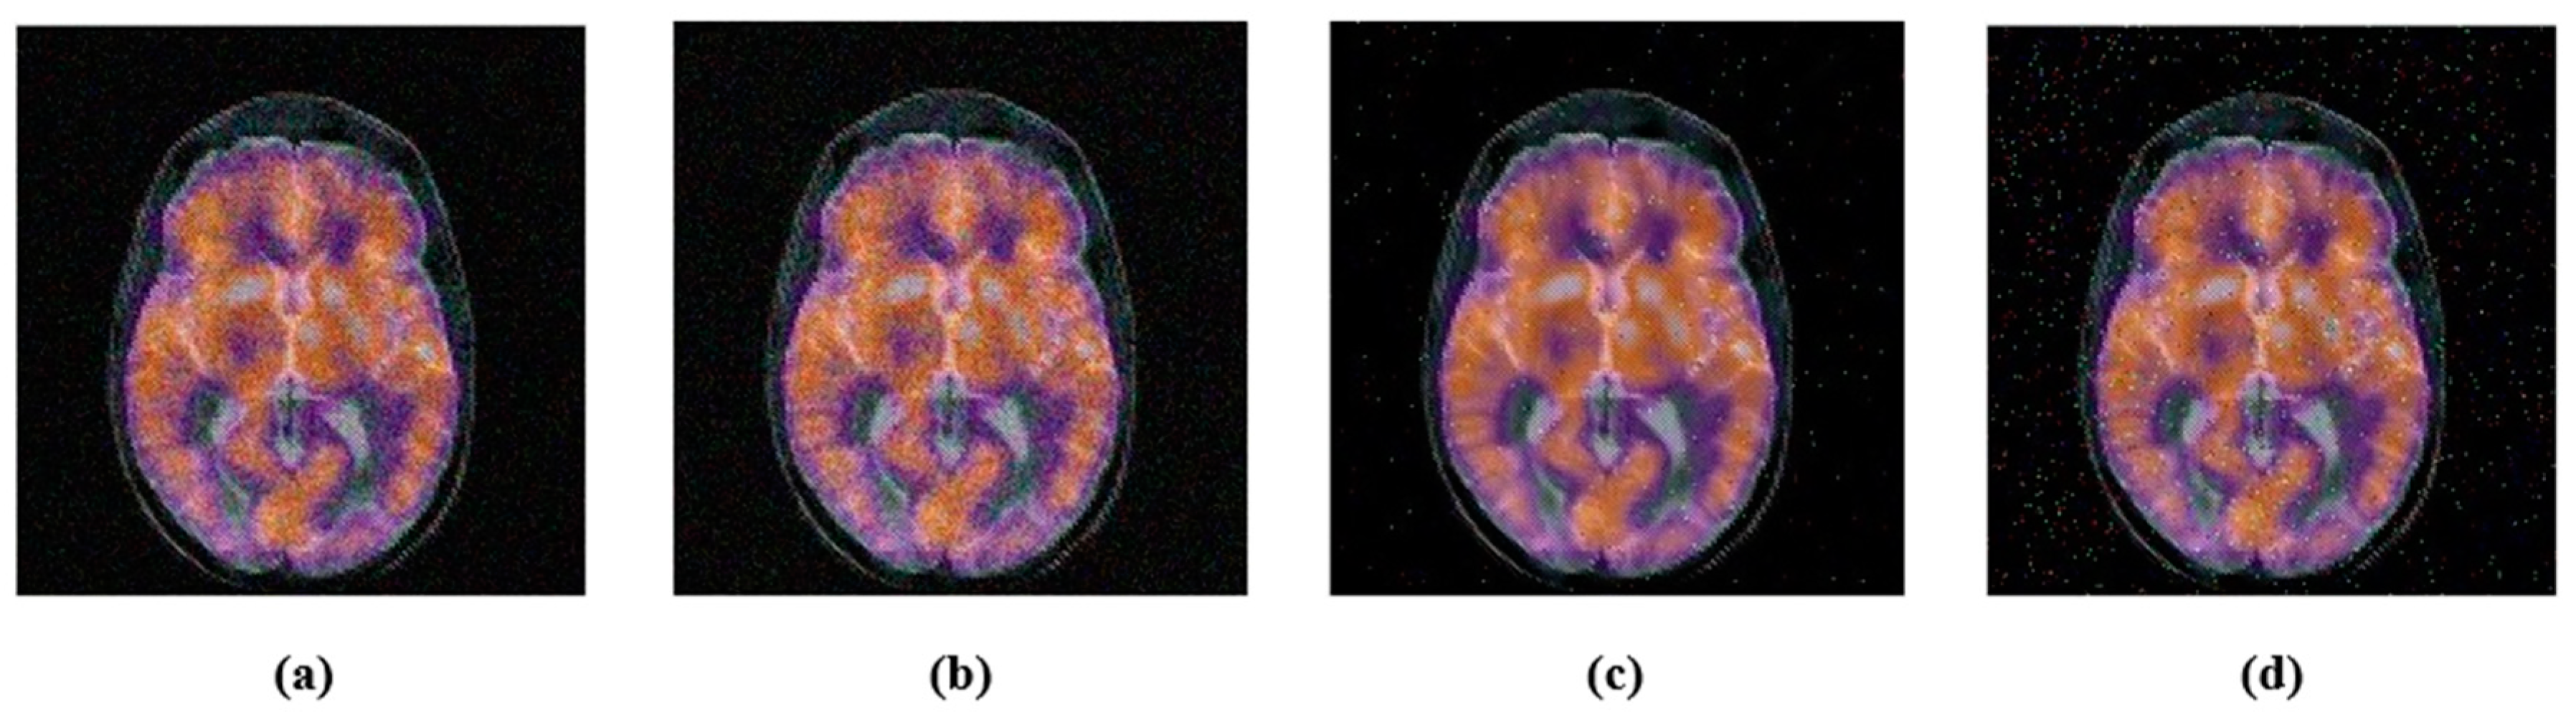

4.2.2. Geometric Attacks